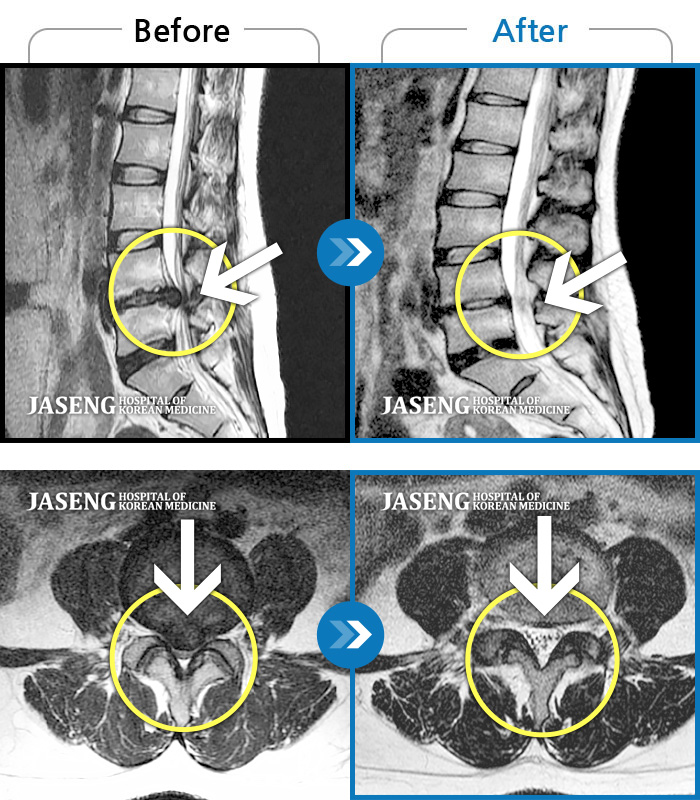

허리디스크

인천 · 조남훈 원장

처음 내원 시 요통, 좌측 하지 방사통으로 인해 통증이 심했습니다.

촬영시기

2022.05.31 ~ 2023.02.07

2023.02.24